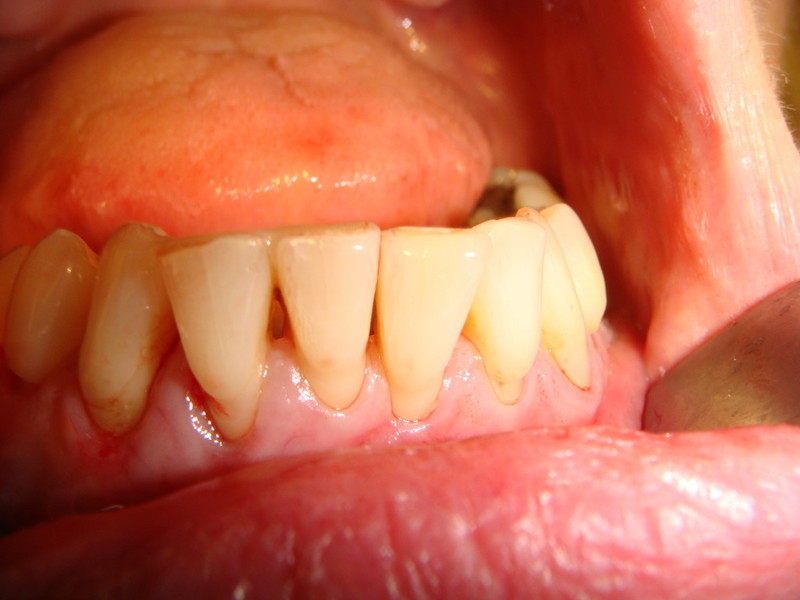

Rigenerazione Gravi difetti parodontali

Rigenerazione difetto parodontale di un canino inferiore con materiale eterologo